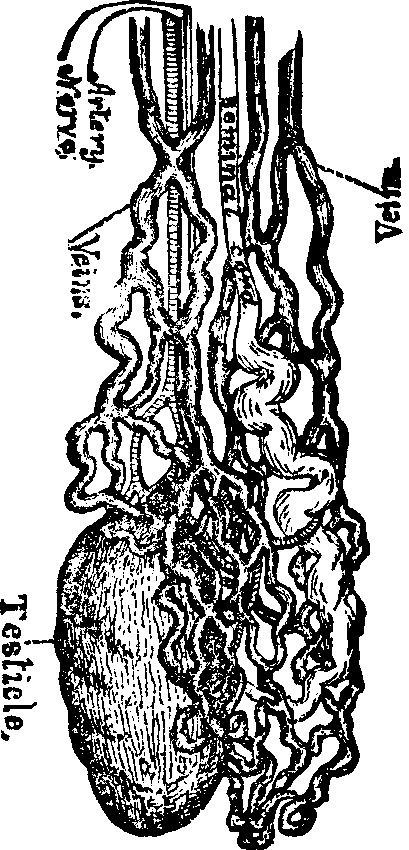

The function of the ovaries is to furnish ova or germs, and the functions of the uterus or womb are to secrete mucus; to exude the menses; to secrete the decidua; to contain and nourish the foetus and to effect its expulsion.